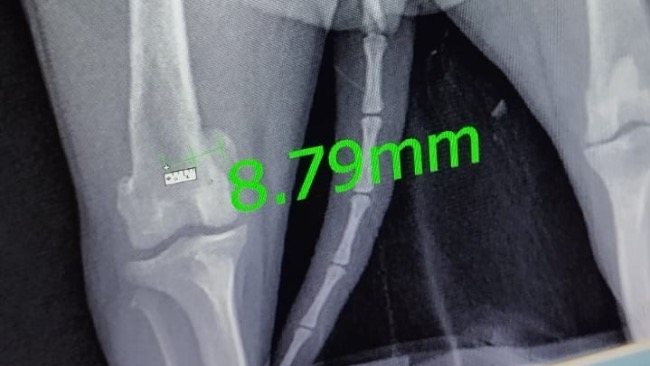

Kochani, pod naszą opiekę trafiła młodziutka szpicka. Niestety podczas konsultacji ortopedycznej okazało się, że jej łapka jest do natychmiastowej operacji. Zamiast radosnego życia młodziutkiego psa, żyje z permanentnym bólem, który uniemożliwia jej normalne poruszanie się. Bella praktycznie cały czas porusza się na trzech łapkach. Koszt operacji 3500-4000zl. Nie mamy wyjścia, musimy zrobić operację. Sunia cierpi, praktycznie nie używa łapki, z powodu ogromnego bólu. Niestety termin operacji jest uzależniony od tego, jak szybko uda nam się zebrać potrzebną kwotę… Liczy się czas i dosłownie każda wpłacona złotówka. Bardzo prosimy was o wsparcie Belli ❤️